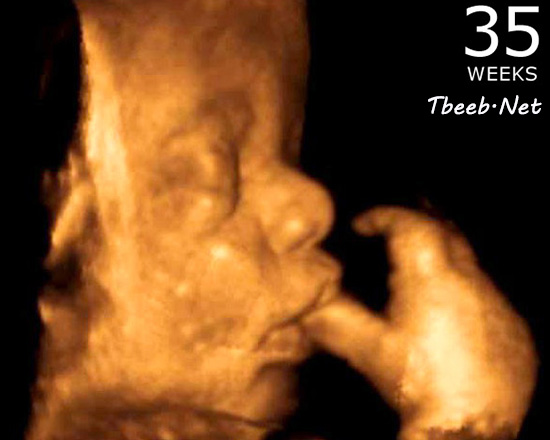

الأسبوع الخامس والثلاثون

يستمر الطفل خلال هذا الأسبوع في اكتساب الوزن وتكديس الدهون في جميع أنحاء الجسم، لا سيما

حول المنكبين, وتشكل الأسابيع الثلاثة اللاحقة الفترة التي يزداد فيها وزن الطفل بأقصى سرعة, وذلك بزيادة قدرها نصف رطل (225 غ) أسبوعيا.

وقد تشعرين بحركة أقل لطفلك في هذا الأسبوع بسبب حالة الانحشار الحاصلة داخل الرحم؛ إذ ربما تجعل تلك الحالة من الصعب على ذلك الطفل الأكثر قوة وحجما أن يقوم ببعض اللكمات, ولكن ربما تشعر الأم بالكثير من التمطط والدحرجة والتلوي.

ربما يكون في هذا الأسبوع قد اكتمل نمو الجلد المجعد، ولو قدر لك استراق النظر إلى طفلك في هذا الأسبوع لرأيت طفلا يمكنك وصفه بأنه ممتلئ الجسم مع وجه صغير مكتمل الاستدارة, ويكمن السبب وراء امتلاء وجه الطفل في الدهون المتراكمة منذ وقت قصير، بالإضافة إلى عضلات المص الناضجة بشكل جيد والجاهزة للعمل.